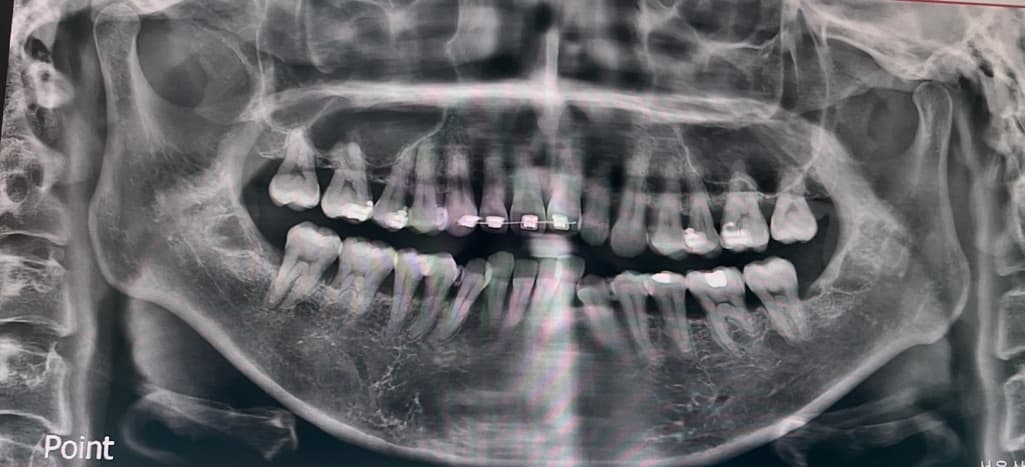

엑스레이 전체적인 치아상태 좀 봐주세용

교정진행중이라 일부만 달고 나머지는 곧 다는데요

잇몸이안좋아보이는데 교정하기 괜찮은가요 전체적인상태가 어때보이시나요?

잇몸뼈의 상태나 치아 뿌리의 상태 등이 아주 건강한 편은 아닙니다. 교정치료는 가능합니다.

치아 뿌리들이 짧고 30대에 교정을 한다면 잇몸이 안좋아질 가능성이 높으니 관리를 철저히 하시는게 좋을것같습니다.

브라켓이 부착되어 있는 파노라마 사진으로는 교정상태나 치아 상태를 정확하게 확인하기 어렵습니다.

나이에 비해 잇몸뼈 높이가 낮은편입니다. 잇몸과 잇몸뼈는 한번 낮아지면 재생이 어렵고, 교정으로 인해 퇴축이 가속화될 수 있습니다

교정 전 잇몸관련하여 치주과 의사와도 상담받아보세요